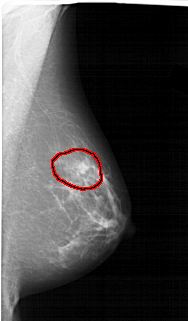

A_1456_1.LEFT_MLO

LEFT_MLO LINES 6871 PIXELS_PER_LINE 3121 BITS_PER_PIXEL 12 RESOLUTION 43.5 NON_OVERLAY

FILE: A_1456_1.RIGHT_MLO.OVERLAY

TOTAL_ABNORMALITIES 1

ABNORMALITY 1

LESION_TYPE MASS SHAPE IRREGULAR MARGINS ILL_DEFINED

ASSESSMENT 4

SUBTLETY 2

PATHOLOGY BENIGN

TOTAL_OUTLINES 1

BOUNDARY